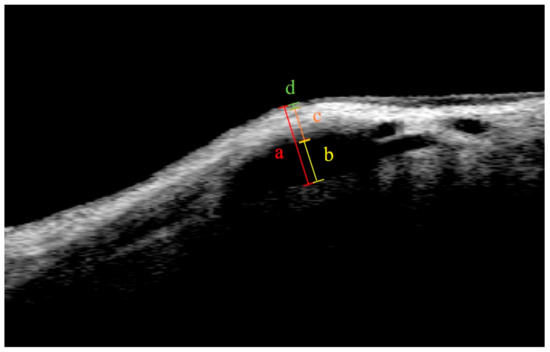

2.4. Bleb Assessment Using AS-OCT